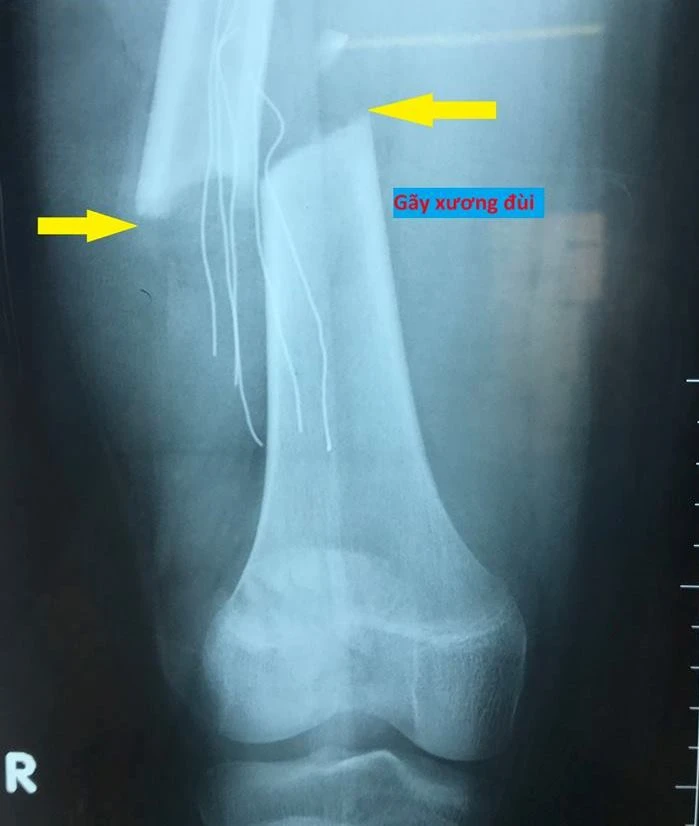

Liền sau đó, bé được sơ cứu và đưa đến BV Đa khoa Xuyên Á, sau đó chuyển BV Nhi đồng 2. Kết quả hình ảnh chụp cắt lớp và cộng hưởng từ cho thấy bệnh nhi bị gãy xương đùi phải, gãy xương gót chân trái, gãy xương hàm trên và hàm dưới, tổn thương mô mềm vùng mặt. May mắn là không có tổn thương não nặng, tri giác bệnh nhân tỉnh táo nhưng không nhớ được nguyên nhân tai nạn.

Hình ảnh chụp cho thấy bệnh nhân bị gãy xương đùi. Ảnh: BV